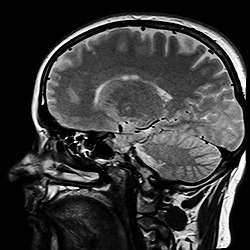

遷延性意識障害は脳死とは違い、生命維持に必要な脳幹などにはダメージがなく、意識や記憶を司る大脳部分に障害があることを指すため、もし何らかの方法でこれらの障害を取り除いたり、停止している大脳の機能を動かすことができれば、遷延性意識障害から回復します。